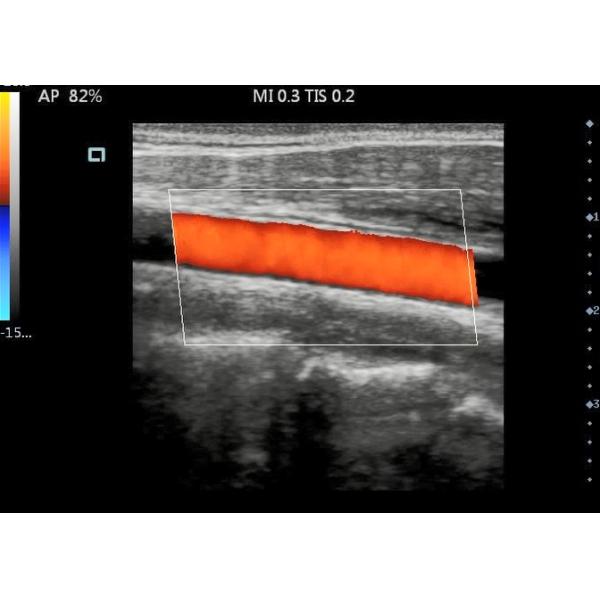

Modes : B,M,2B,B/M,4B,C,PW, Power,DirPower,THI

| Modes | B,B/B,B/M,CFM,CFM/B,PDI,PDI/B,PW.CW |

15 Inches Color Doppler Ultrasound Scanner Machine High Resolution LCD Screen Images |